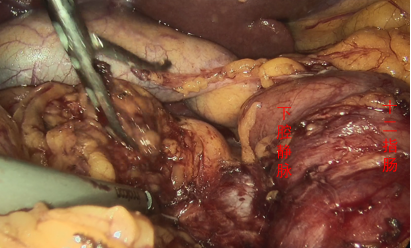

图为:腹腔镜下游离出下腔静脉

图为:腹腔镜下游离出双侧肾静脉,右侧肾上腺静脉,右侧生殖静脉,下腔静脉近心端上血管吊带

图为:腹腔镜下结扎可见腰静脉,哈巴狗阻断近心端及远心端下腔静脉,可见滤器远端回收勾,此处剪开下腔静脉